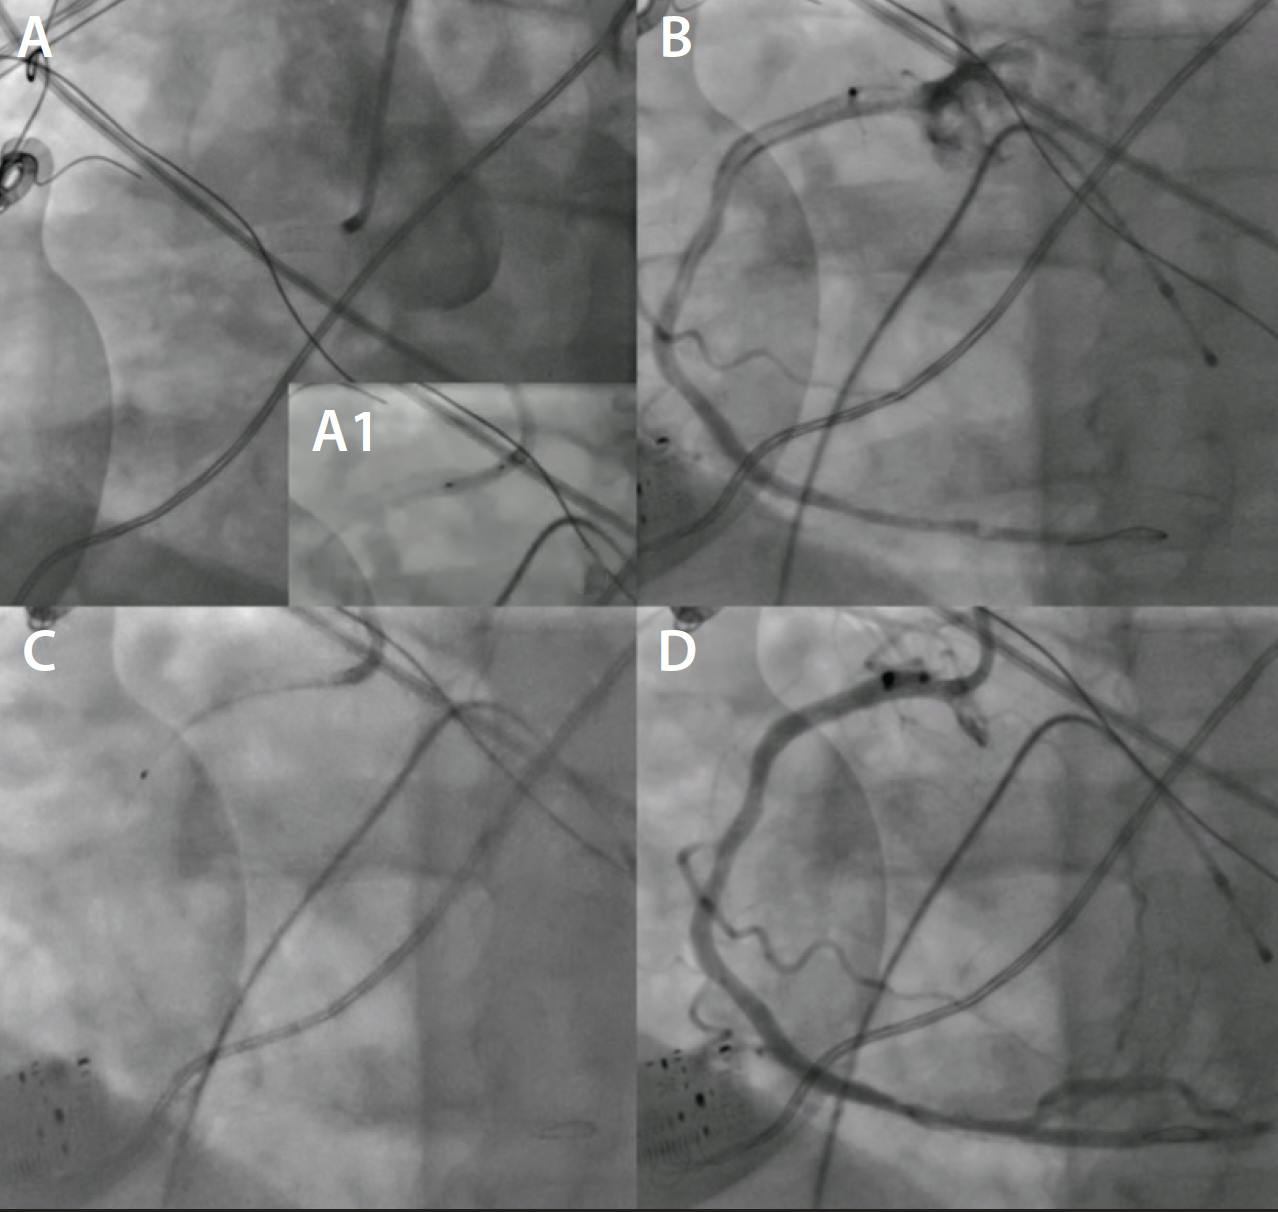

• GP IIb/IIIa. Data have historically been conflicted regarding the IV versus IC route.21-22 I usually give it intravenously but have utilized the IC route more recently in a few severe cases, observing a rapid and positive effect (Figure 1). A recent meta-analysis including 22 RCTs and > 7,000 patients found statistically significant differences in TIMI flow, myocardial blush grade, ST-segment resolution, major adverse cardiovascular events, and 1-month heart failure rehospitalization favoring IC administration, with equipoise in short-term bleeding and mortality rates.23

Figure 1. Aorto-ostial stent thrombosis in the right coronary artery (A) and predilatation with a 2.5-mm semicompliant balloon (A1). High thrombus burden throughout proximal and mid right coronary artery (B), treated with multiple manual AT runs and IC tirofiban (C). Final result showing thrombus resolution and TIMI grade 3 flow (D).